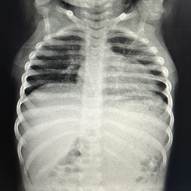

Al mes de haber suspendido tratamiento, presenta RAE: 5.220/mm3 por lo que reinicia meprednisona 1 mg/kg/día vía oral. Con laboratorio control a los 11 días y RAE en descenso se decide descender glucocorticoide para evitar efectos adversos a largo plazo hasta suspenderlo y asociar hidroxiurea a 15 mg/kg/día vía oral como ahorrador de glucocorticoide. Se cita al paciente cada 10 días para evaluar curva de descenso de RAE. En los controles posteriores el paciente comienza a desmejorar, presentando anemia con requerimiento transfusional, RAE: 5.600/mm3, ERS y PCR en ascenso, agrega síndrome febril intermitente y compromiso respiratorio. Se diagnostica neumonía unifocal izquierda. Se realizaron hemocultivos, que fueron negativos, y aspirado para gérmenes comunes y COVID. que fue negativo. Se realiza TAC de tórax donde se observa imagen compatible con neumopatía infiltrativa. Se realiza lavado broncoalveolar, observándose infiltrado eosinofílico 60% con cultivo negativo para Aspergilosis asociada a eosinofilia en contexto de tratamiento inmunosupresor.